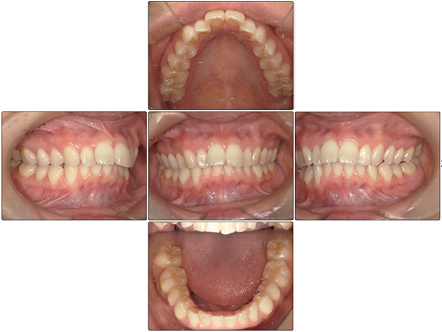

お口の中全体の写真

Before

- 上の前歯が出っ歯なのが気になるということで矯正治療の相談をされた方です。

上の前歯の出っ歯以外にも上下の前歯に叢生を認め、咬合関係のズレも認めました。